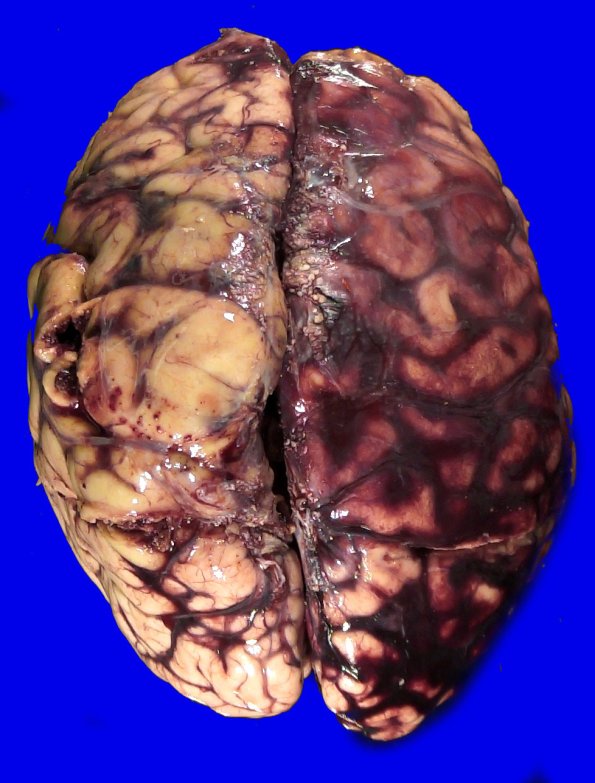

Washington University Experience | VASCULAR | Hemorrhage, hypertensive | 49B1 A20-76_4

The right hemisphere shows subarachnoid hemorrhage.